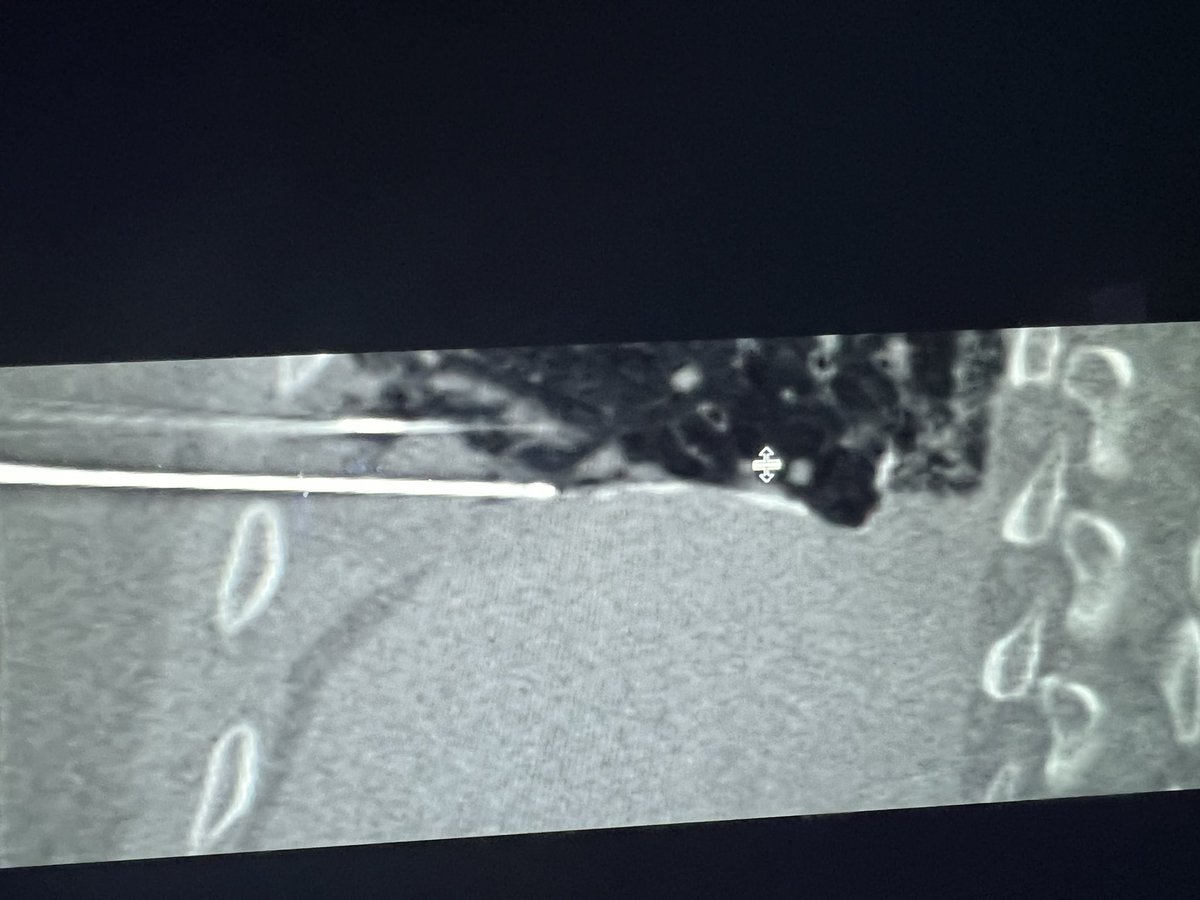

C-TRACT: a vital study for chronic blood clots. Visit bloodclotstudy.wustl.edu/c-tract/ to learn more. #patientcare #bloodclots #clinicalresearch #DVT